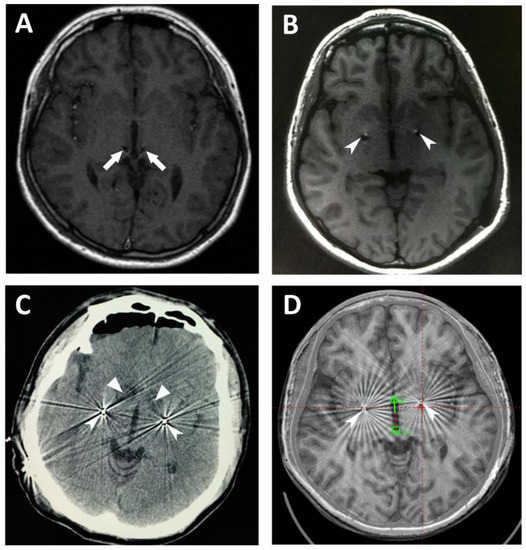

The post-op MRI, CT, and fused images of the pre-op MRI and post-op CT helped to confirm the location of the radiofrequency lesions and the implanted leads. The accuracy of the lesions and the lead placements were verified in the thirteen patients. Figure 1 demonstrates the location of the leads and lesions on post-op MRIs and CTs of Cases 6–8 and 13. The locations of the DBS leads on post-op imaging data of Cases 9–12 are presented in Figure S1.

Figure 1. Location of the leads and lesions on postoperative MRIs and CTs. (A) Case 6, magnetic resonance imaging (MRI) scan of the brain after lead implantation, demonstrating the bilateral leads in the centromedian–parafascicular complex (CM-Pf); (B) Case 7, brain MRI scan after lead implantation, showing the bilateral leads in the globus pallidus internus (GPi); (C) Case 8, computed tomography (CT) scan of the brain after ablation and lead implantation, demonstrating the bilateral lesions in the anterior limb of the internal capsule (ALIC) and the bilateral leads in the GPi; (D) Case 13, fusion of the postoperative CT with preoperative MRI, demonstrating the bilateral leads in the GPi. The arrows denote CM-Pf, the arrowheads denote GPi, and the triangles denote ALIC.